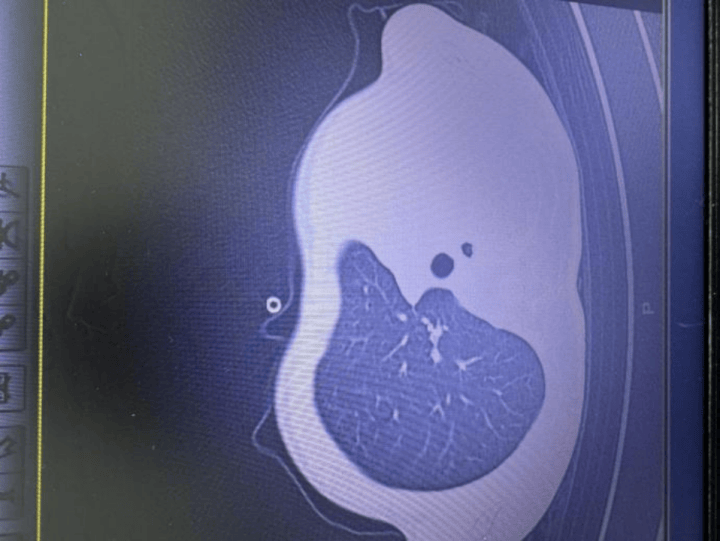

急诊检查结果让医护人员瞬间紧张:验血显示炎症指标大幅上升,胸片发现左侧肺叶几乎不工作了,影像学中变成大片白色,即通常所说的“白肺”,意味着肺功能严重受损,孩子已经缺氧,随时有窒息危险皇冠信用网正版 。

图:影像显示肺白皇冠信用网正版 了一半

“这是流感合并细菌感染引起的严重肺炎,同时发生了坏死性喉气管支气管炎,并有严重并发症,若不及时处理,几小时就可能威胁生命!”杨医生回忆皇冠信用网正版 。